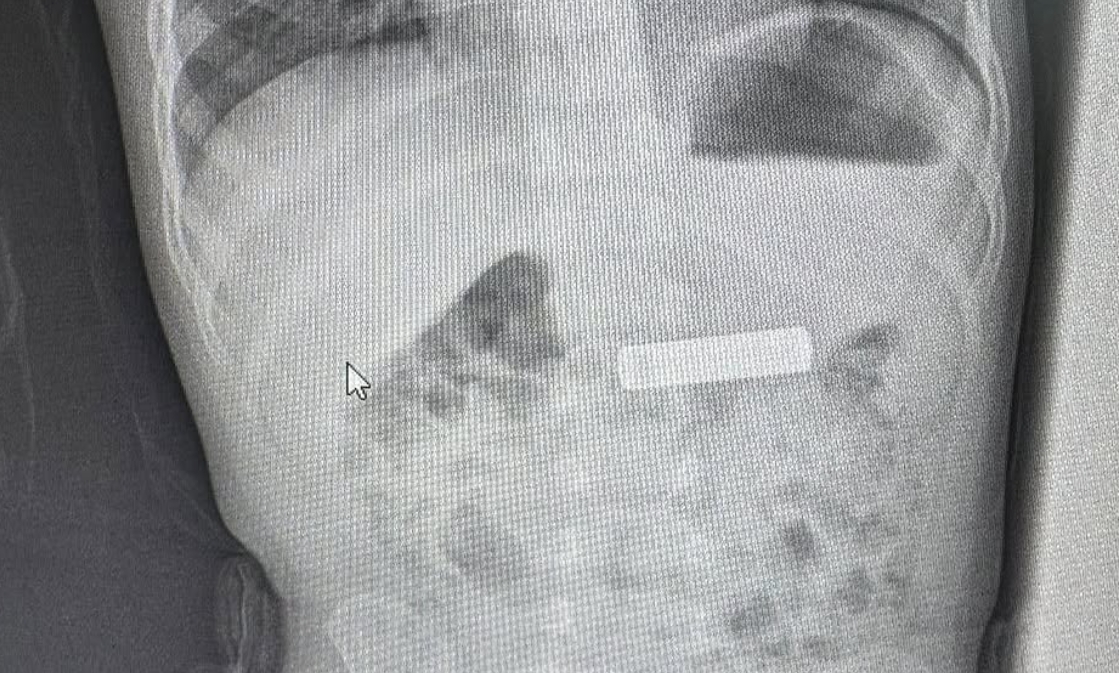

Гастроентерологот Бесник Елези успешно извадил батерија од далечински управувач од стомакот на двегодишно дете во Гњилане, Косово.

„На двегодишното дете К.Ш му е извадена батеријата на далечинскиот управувач од стомакот“, напиша Елези споделувајќи неколку фотографии од постапката.